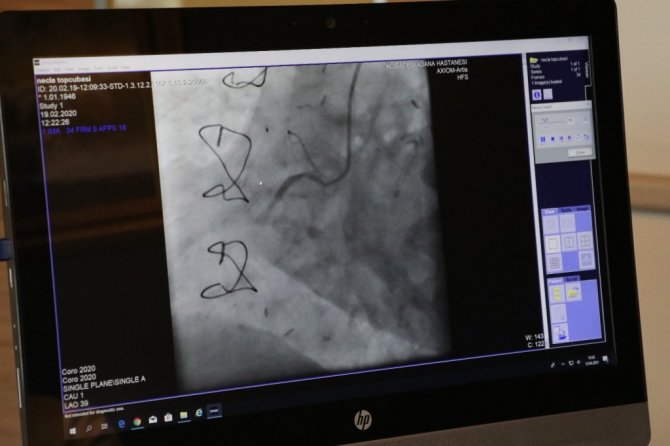

"Yapılan çalışmalar, bu ilaçların kesinlikle zararının olmadığını ve ilaçlara devam etmemiz gerektiğini ortaya koydu. Covid-19 pandemisinin ilk görüldüğü aylarda, hastanelerin yataklarını ve kaynaklarını korona hastalarında kullanmak amacıyla koroner anjiyografiler, kalp krizi dışında ertelendi. Hastaneye gelen kalp krizi ve kalp yetmezliği vakalarında ciddi bir düşüş oldu. Fakat kalp hastalıklarına bağlı ölüm oranı arttı. Birçok hasta hastaneye gelmek istemediği için hayatını kaybetti."